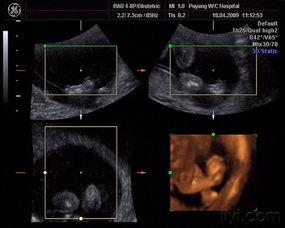

二、怀孕3个月胎儿图片赏析

接下来,让我们一起欣赏一些怀孕3个月胎儿图片,感受宝宝的成长变化。

1. 宝宝的脸部:从图片中可以看到,宝宝的脸部轮廓已经非常清晰,眼睛、鼻子、嘴巴等面部特征都开始显现。

2. 宝宝的四肢:宝宝的四肢开始变得更有力,手指和脚趾也开始分开,看起来就像一个小小的游泳运动员。

3. 宝宝的器官:通过图片可以看到,宝宝的器官正在逐渐发育,尤其是心脏,跳动得非常有力。

4. 宝宝的性别:有些图片中,宝宝的性别已经可以辨认出来,让人既期待又好奇。